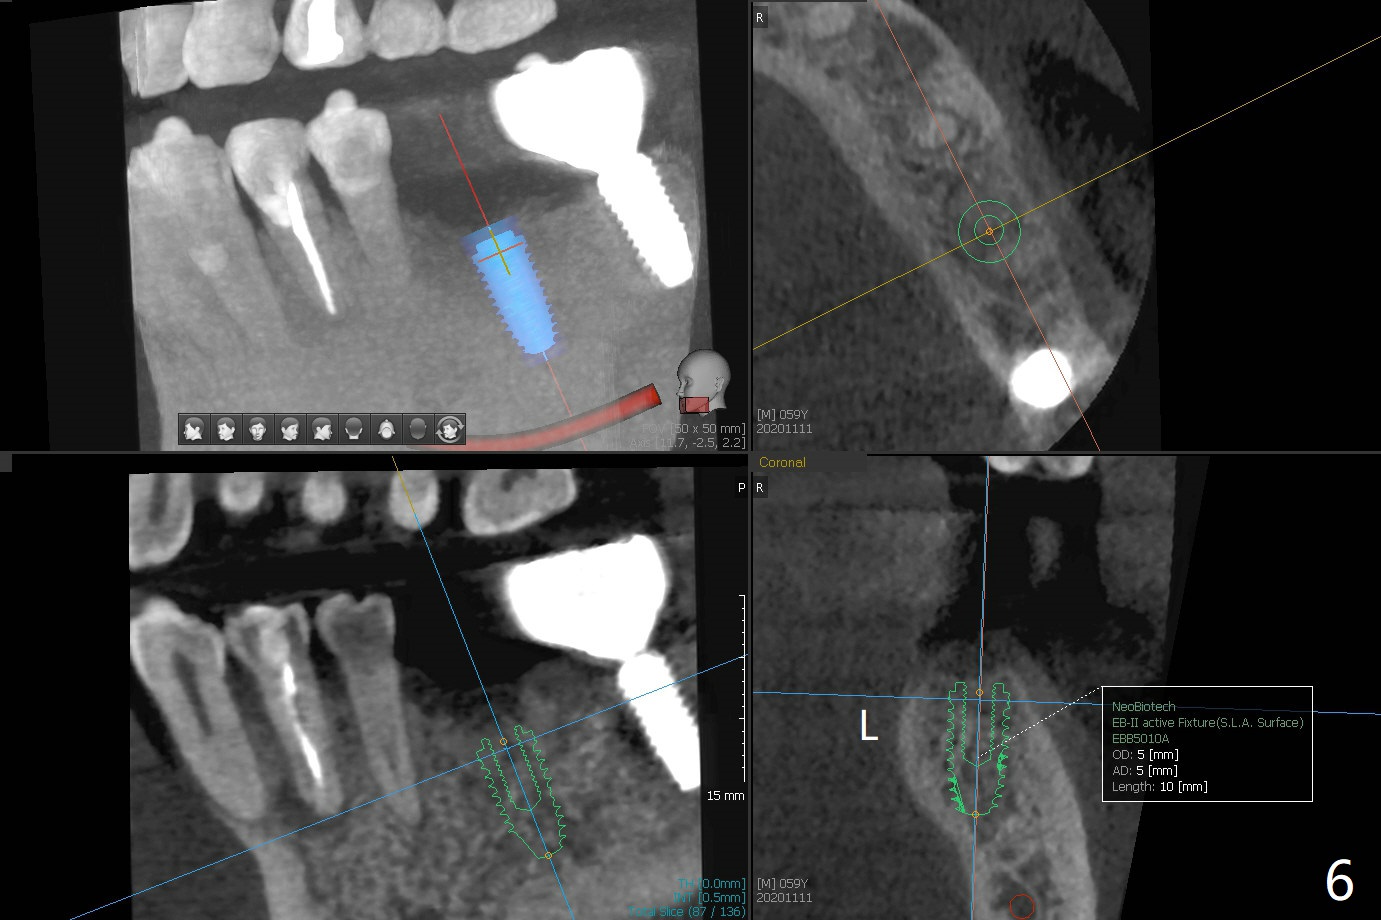

A 58-year-old man requests extraction of the tooth #19 with supraocclusion (Fig.1). After extraction, the septal gingiva has to be sectioned to remove underlying granulation tissue thoroughly. The buccal plate is missing. Ossogen (allograft, Fig.2 *) is placed around the septum (red dashed line). The socket opening is covered by BioXclude and approximated with 4-0 PGA suture, followed by periodontal dressing. With the septum's support, bone graft is expected to heal without too much ridge collapse. The mesial and distal sockets behave as 2 small premolar ones, getting ample blood supply. The socket heals in 20 days (Fig.3). The sockets heal with preservation of the septum (Fig.4: S), while there is formation of the cortical plate on the top of the ridge 10 months postop (Fig.5: ^). It is safe to place a 5x10 mm implant with guide (Fig.6), whereas it may be necessary to place bone graft lingual to the implant at #18 associated with free hand surgery (Fig.7: >). Return to Lower Molar Immediate Implant, No Deviation 18 种植 位点保存 Xin Wei, DDS, PhD, MS 1st edition 01/22/2020, last revision 07/03/2021